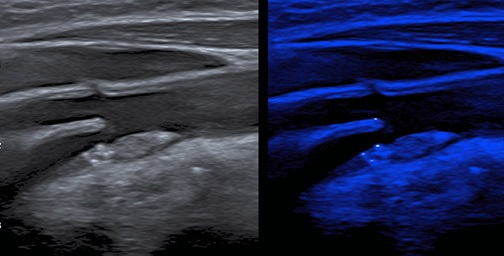

- Впервые применена новая ультразвуковая технология MicroPure для выявления микрокальциноза в атеросклеротической бляшке (АСБ) сонной артерии у пациентов с острым коронарным синдромом и стабильной ишемической болезнью сердца.

- У пациентов с острым коронарным синдромом микрокальцинаты в АСБ сонной артерии встречаются чаще, чем у пациентов с ишемической болезнью сердца.

- Выявление микрокальцинатов с помощью ультразвукового исследования может быть важным признаком нестабильности АСБ.

Цель. Оценить возможности ультразвуковой технологии MicroPure для выявления микрокальциноза в атеросклеротической бляшке (АСБ) сонной артерии у пациентов с острым коронарным синдромом (ОКС).

Материал и методы. Обследовано 50 пациентов с сердечно-сосудистыми заболеваниями (65,62±11,12 лет, 34 муж.), из них 25 пациентов ОКС (64,0±11,5 лет, 19 муж.) и 25 пациентов с хронической ишемической болезнью сердца (ИБС) (67,2±10,7 лет, 15 муж.). Пациентам было проведено стандартное клиниколабораторное обследование и ультразвуковое исследование сонных артерий на системе Canon Aplio a550 (Япония) с линейным датчиком с частотой 14,0 МГц. Сканирование выявленных АСБ проводили в В-режиме и режиме MicroPure для анализа микрокальцинатов (МК). Оценивали факт наличия МК в АСБ, количество МК (единичные или множественные), локализацию МК в АСБ (в покрышке, в теле, в основании, сочетанная локализация).

Результаты. МК в АСБ были выявлены у всех пациентов с ОКС, тогда как в группе пациентов с ИБС в 2 раза реже (100% vs 48%, p=0,0001). МК чаще выявлялись в покрышке и в теле АСБ у пациентов группы ОКС, чем в АСБ пациентов группы ИБС (43% vs 23%, р=0,0125 и 55,4% vs 14,6%, р<0,001, соответственно). В обеих группах выявлялись как единичные, так и множественные МК, в группе ОКС 26,3% и 73,7%, в группе ИБС 28,12% и 71,8%, соответственно (р>0,05).

Заключение. У пациентов с ОКС выявлено статистически значимое преобладание МК АСБ сонных артерий по сравнению с пациентами с ИБС. Выявление МК с помощью новых ультразвуковых технологий может быть важным признаком нестабильности АСБ.